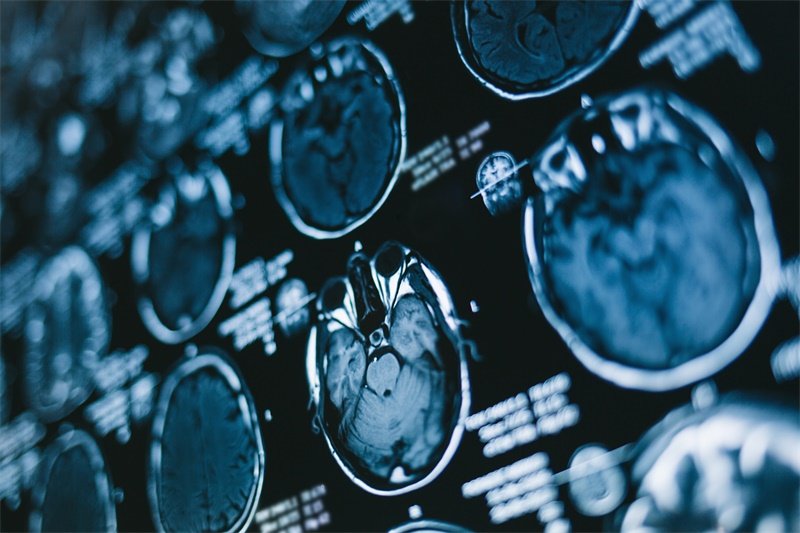

为了确诊蝶鞍区的占位性病变,医生会综合考虑患者的临床症状、影像学检查与实验室检查。常用的影像学检查方法包括CT和MRI。

影像学检查

CT扫描能够快速地评估病变的大小与位置,并初步判断其性质。而MRI则提供了更详细的软组织对比,帮助识别肿瘤的扩散、压迫等情况。

蝶鞍区肿瘤的影像学特征有哪些?

CT和MRI是评估蝶鞍区肿瘤的重要工具。CT能显示肿瘤的边缘、大小以及钙化情况,而MRI则能够更清晰地显示肿瘤对周围结构的影响、肿瘤的水肿及其与脑组织的关系,这些信息对于医生制定治疗方案至关重要。